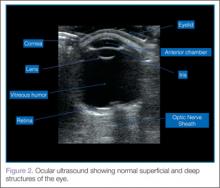

When performing ocular ultrasound, it is recommended that the clinician should scan/sweep the normal eye first and then the abnormal eye. Figure 2 demonstrates the ocular structures easily visualized by ultrasound.. Both eyes should be imaged in at least 2 planes. In addition, the patient should be instructed to look through all of the cardinal positions of gaze to maximize the ocular structures visualized.